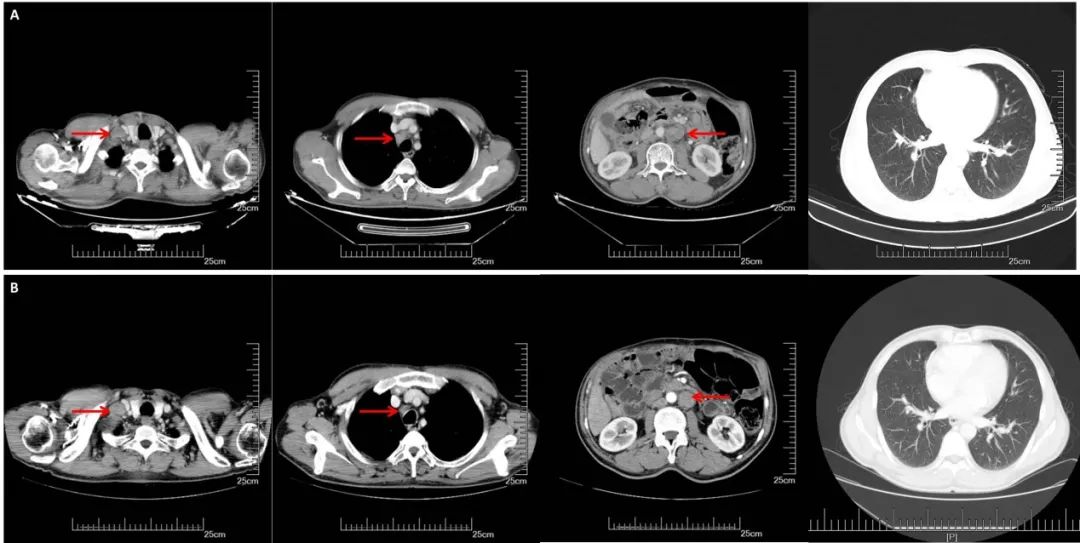

A:CT增强(2017.09.29):右锁骨上,纵膈,腹腔淋巴结明显增大,双肺无明显变化;B:CT增强(2018.03.27):腹膜后多发增大淋巴结较前缩小,右侧锁骨上纵隔内见多发淋巴结,部分较前增大,双肺较前变化不大。

2018.4.10~6. 5给予右锁骨上、纵隔及腹膜后转移淋巴结放疗DT:50. 4Gy/28f,并序贯给予口服阿帕替尼维持治疗(250mg,qd,po),2018.11.7日患者因进食后腹痛,并伴有恶心呕吐,诊断为“肠梗阻”。

CT(2018.11.7):腹膜后多发增大淋巴结影,考虑转移,部分较前增大。双侧锁骨上、双侧隔肌脚后及纵隔内多发增大淋巴结,考虑转移,部分较前、增大。双肺多发小结节,较前增多、增大,转移可能。

CT(2019. 5.16):双侧锁骨上、双侧膈肌脚后间隙、脊柱左旁及纵隔多发淋巴结,部分较前增大:腹膜后及右侧髂血管旁多发淋巴结,部分较前减小。余较前相仿。双肺多发转移瘤。较前增多增大。

CT(2019.10.25):双肺多发转移结节,较前明显增多增大。双侧锁骨上、双侧膈肌脚后间隙、脊柱左旁、纵隔多发肿大淋巴结,较前变化不明显。